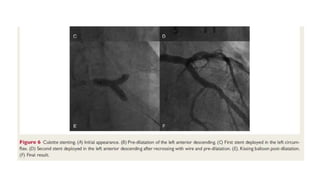

Left main stenting